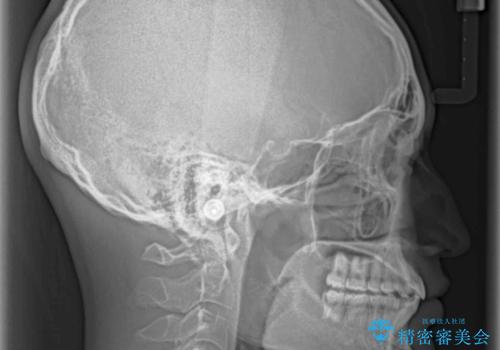

深い咬み合わせとデコボコ ワイヤー矯正で短期治療

インビザラインでの治療も可能でしたが、深い咬み合わせと奥歯の咬み合わせを改善するにあたり、ワイヤー矯正の方が治療期間を短縮できると判断し、ワイヤー矯正をお勧めしました。

結果として、1年かからずに奥歯の咬み合わせを改善することができました。